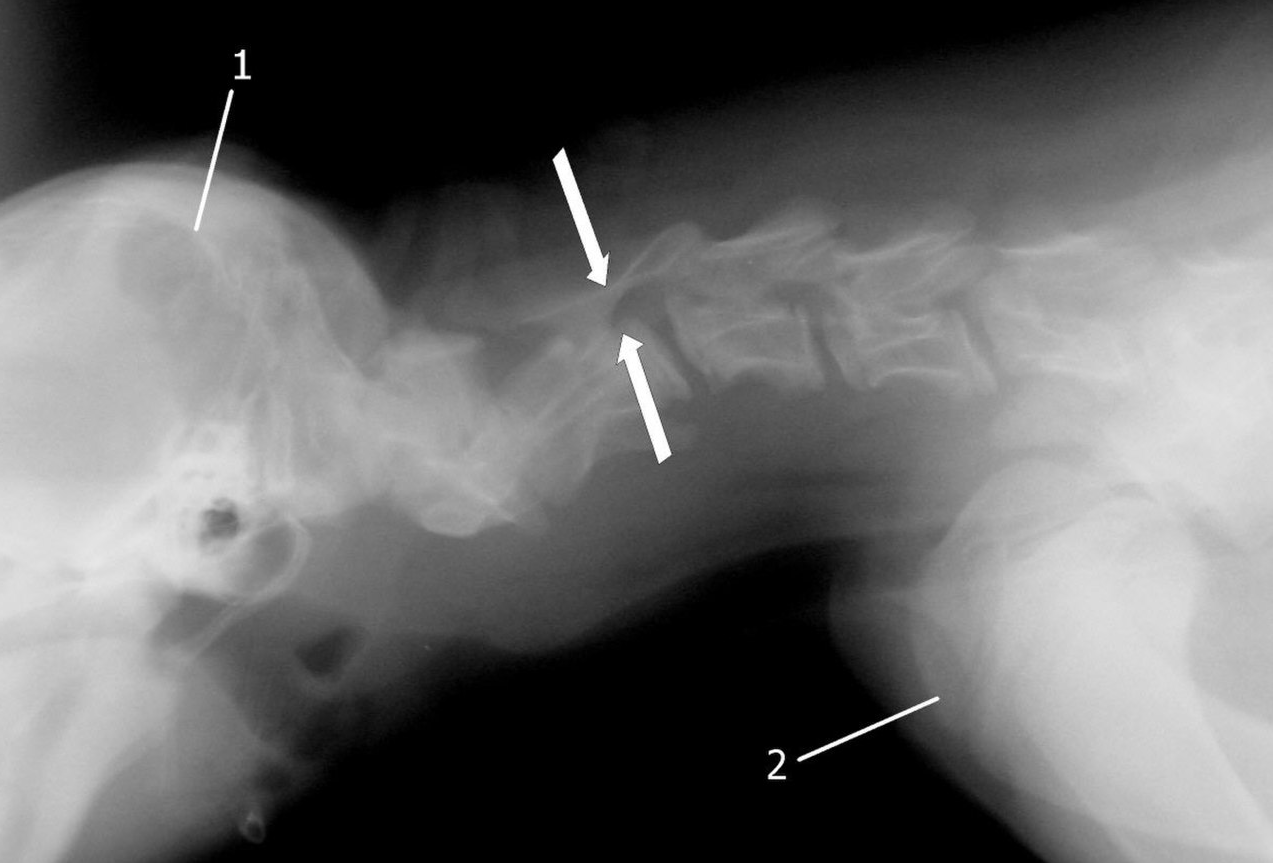

- Синдром Воблера. Дегенеративное заболевание шейных позвонков. Лечится ортопедической или хирургической операцией.

У доберманов крепкое здоровье, но, как и у всех пород, есть недостатки: плохая свертываемость крови, проблемы со зрением, дисплазия тазобедренных суставов (особенно у пожилых собак), заболевания щитовидной железы и сердечной мышцы. Это альбинизм или даже рак.